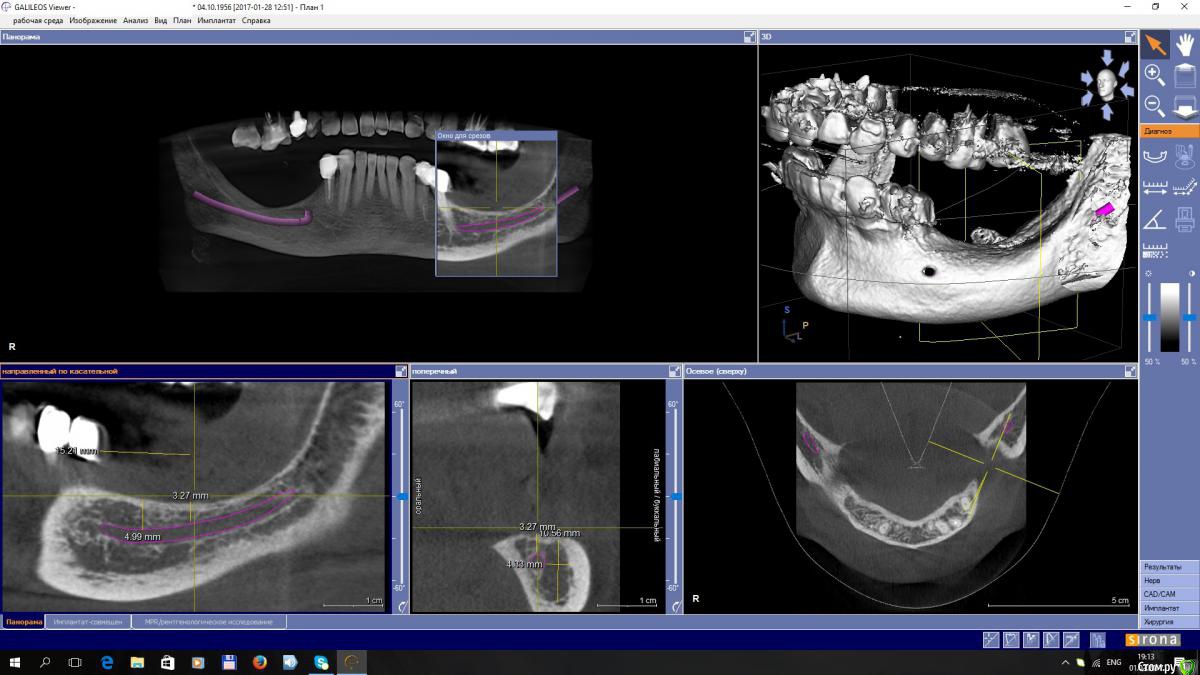

EEcho Опубликовано 3 февраля, 2017 Поделиться Опубликовано 3 февраля, 2017 Уважаемые коллеги! Я в раздумье.Максимально, кость я могу поднять на 4-5 мм, с одной и с другой стороны. Дальше не позволяет межальвеолярная высота.Делать репозицию нерва или все таки пластику с последующей постановкой коротких имплантов. Ссылка на комментарий

Dman Опубликовано 13 февраля, 2017 Поделиться Опубликовано 13 февраля, 2017 Дальше не позволяет межальвеолярная высота. почему не позволяет? попросите ортопеда, пусть спилит/покроет коронками выдвинувшиеся антагонисты Ссылка на комментарий